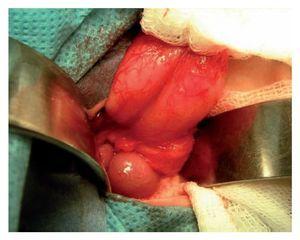

Se incluyeron 41 pacientes, 22 (55%) fueron del género masculino y 18 del género femenino (45%). Treinta y cinco (85%) eran originarios del Distrito Federal y 6 (15%) del Estado de México. El peso promedio al nacimiento fue 2,650 gramos y 24 fueron de término. La manifestación clínica constante fue vómito biliar, ya que se presentó en todos los pacientes. La imagen radiográfica de doble burbuja causada por la dilatación gástrica se observó en 31 pacientes (70.5%) (Imagen 1). La causa de la obstrucción duodenal fue atresia duodenal en 35 casos (86%) y páncreas anular en 6 (14%) (Foto 1). Todos tenían obstrucción posvateriana, 27 de la segunda porción del duodeno (66%) y 14 de la tercera (34%). Ocho (20%) tuvieron trisomía 21.

Foto 1. Momento transoperatorio que muestra cómo el tejido pancreático envuelve la segunda porción del duodeno, dando lugar a lo que conocemos como páncreas anular.